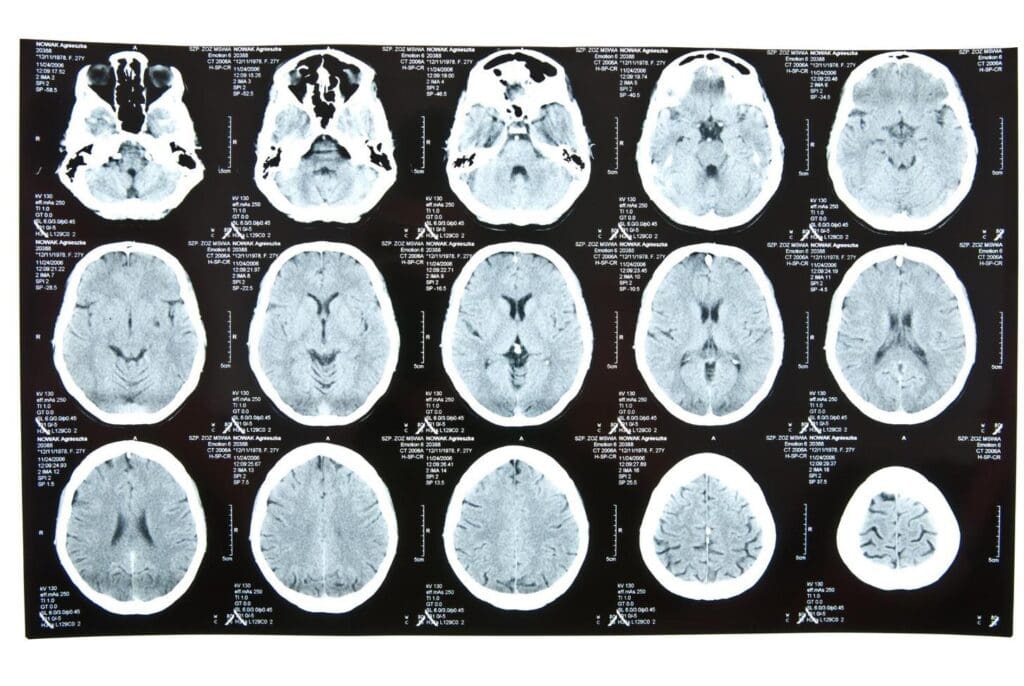

Advances in Neuroimaging and Diagnostics

New neuroimaging techniques are helping us diagnose and track brain cancer better. Advanced MRI and PET scans give us detailed tumor info. For example, MRI radiomics can spot tumor features linked to prognosis.